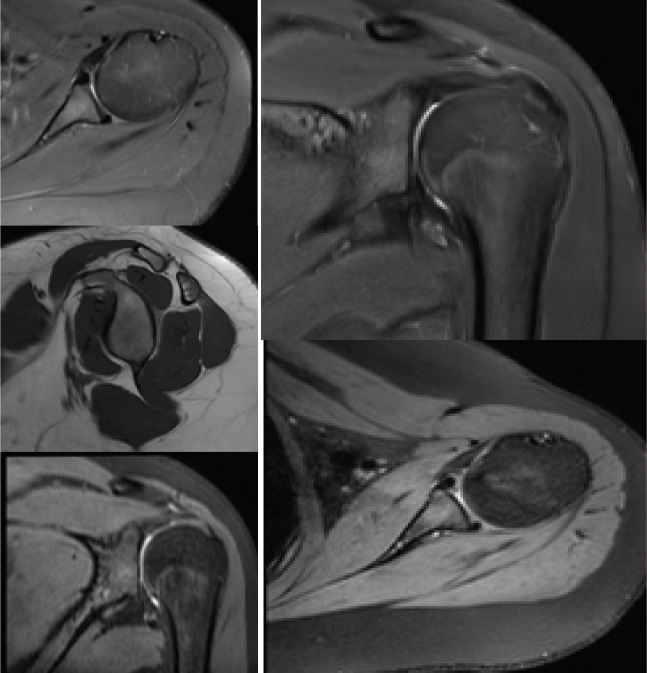

Case report: We report a unique case of a 15-year-old female who presented with chronic, atraumatic left shoulder subluxation, persisting over 18 months. The patient experienced pain and limited range of motion but reported no history of injury. Multiple prior consultations yielded temporary relief with analgesics, and no definitive diagnosis was established. Clinical evaluation revealed limited active abduction and external rotation with no signs of ligamentous laxity or neurological involvement. Radiographic assessment demonstrated gross inferior subluxation of the humeral head. Magnetic resonance imaging and computed tomography imaging confirmed intact soft tissue structures with mild joint effusion, anterior glenoid flattening, and a 6% glenoid bone loss. A diagnosis of inferior, non-positional, controllable idiopathic FSI was made, likely due to deltoid atony.